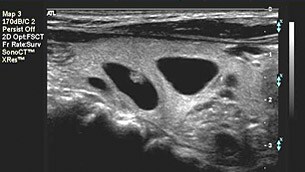

SonoCT imaging technology uses transmit beam-steering techniques to obtain coplanar, tomographic images from different viewing angles, then combines these micro-angulated images into a single compounded image at real-time frame rates. SonoCT imaging enables clinicians to acquire up to nine times more tissue information than the orthogonal beams used in conventional ultrasound, without any unusual manipulation of the transducer and without sacrificing frame rates.

With SonoCT, angle-generated and speckle noise artifacts are reduced, and structures with curved and irregular borders are more readily visualized. Contrast resolution is improved and tissue margins are more discernable. Using SonoCT imaging, real tissue information is reinforced while random artifacts are virtually eliminated. This powerful imaging technology, available on linear, curved, tightly curved, and mechanical volumetric array transducers, produces images superior to conventional imaging in up to 94% of patients. SonoCT imaging has further been proven to boost diagnostic confidence, create operational efficiencies and, in a critically important conclusion, change patient management in as many as 17.6% of cases*.